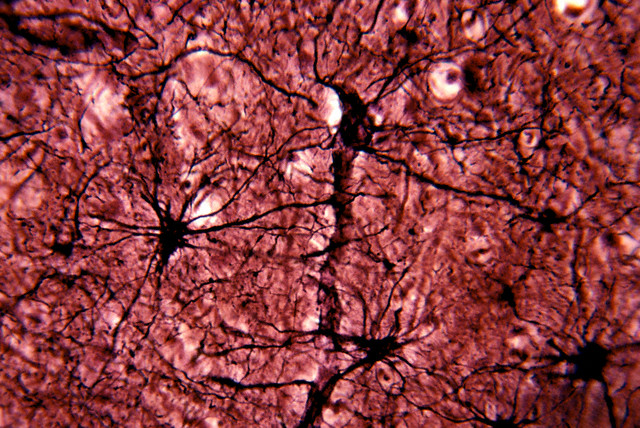

Нейроны (красным, окрашены только тела нейронов, без отростков) и глиальные клетки (зелёным) ядер ствола мозга. (Фото Wellcome Images / https://www.flickr.com/photos/wellcomeimages/6880271012.)Нейроны (красным, окрашены только тела нейронов, без отростков) и глиальные клетки (зелёным) ядер ствола мозга. (Фото Wellcome Images / https://www.flickr.com/photos/wellcomeimages/6880271012.)Глиальные клетки астроциты. (Фото Dr. John D. Cunningham / Visuals Unlimited / Corbis.)Глиальные клетки астроциты. (Фото Dr. John D. Cunningham / Visuals Unlimited / Corbis.)